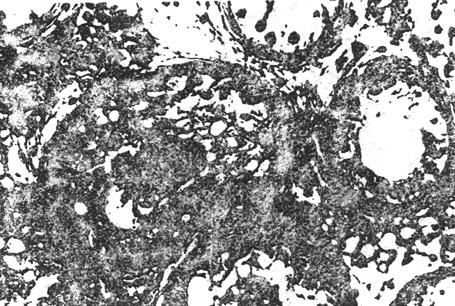

③生精阻滞:其特点是虽有生精细胞,但不能发育成精子。睾丸精子发生可停止在精原细胞,初级精母细胞和精子细胞期,以停止在初级精母期细胞为多见。精液检查虽无精子,但可见脱落的精母细胞。

图8-3-5 生精阻滞,曲细精管内无精子生成